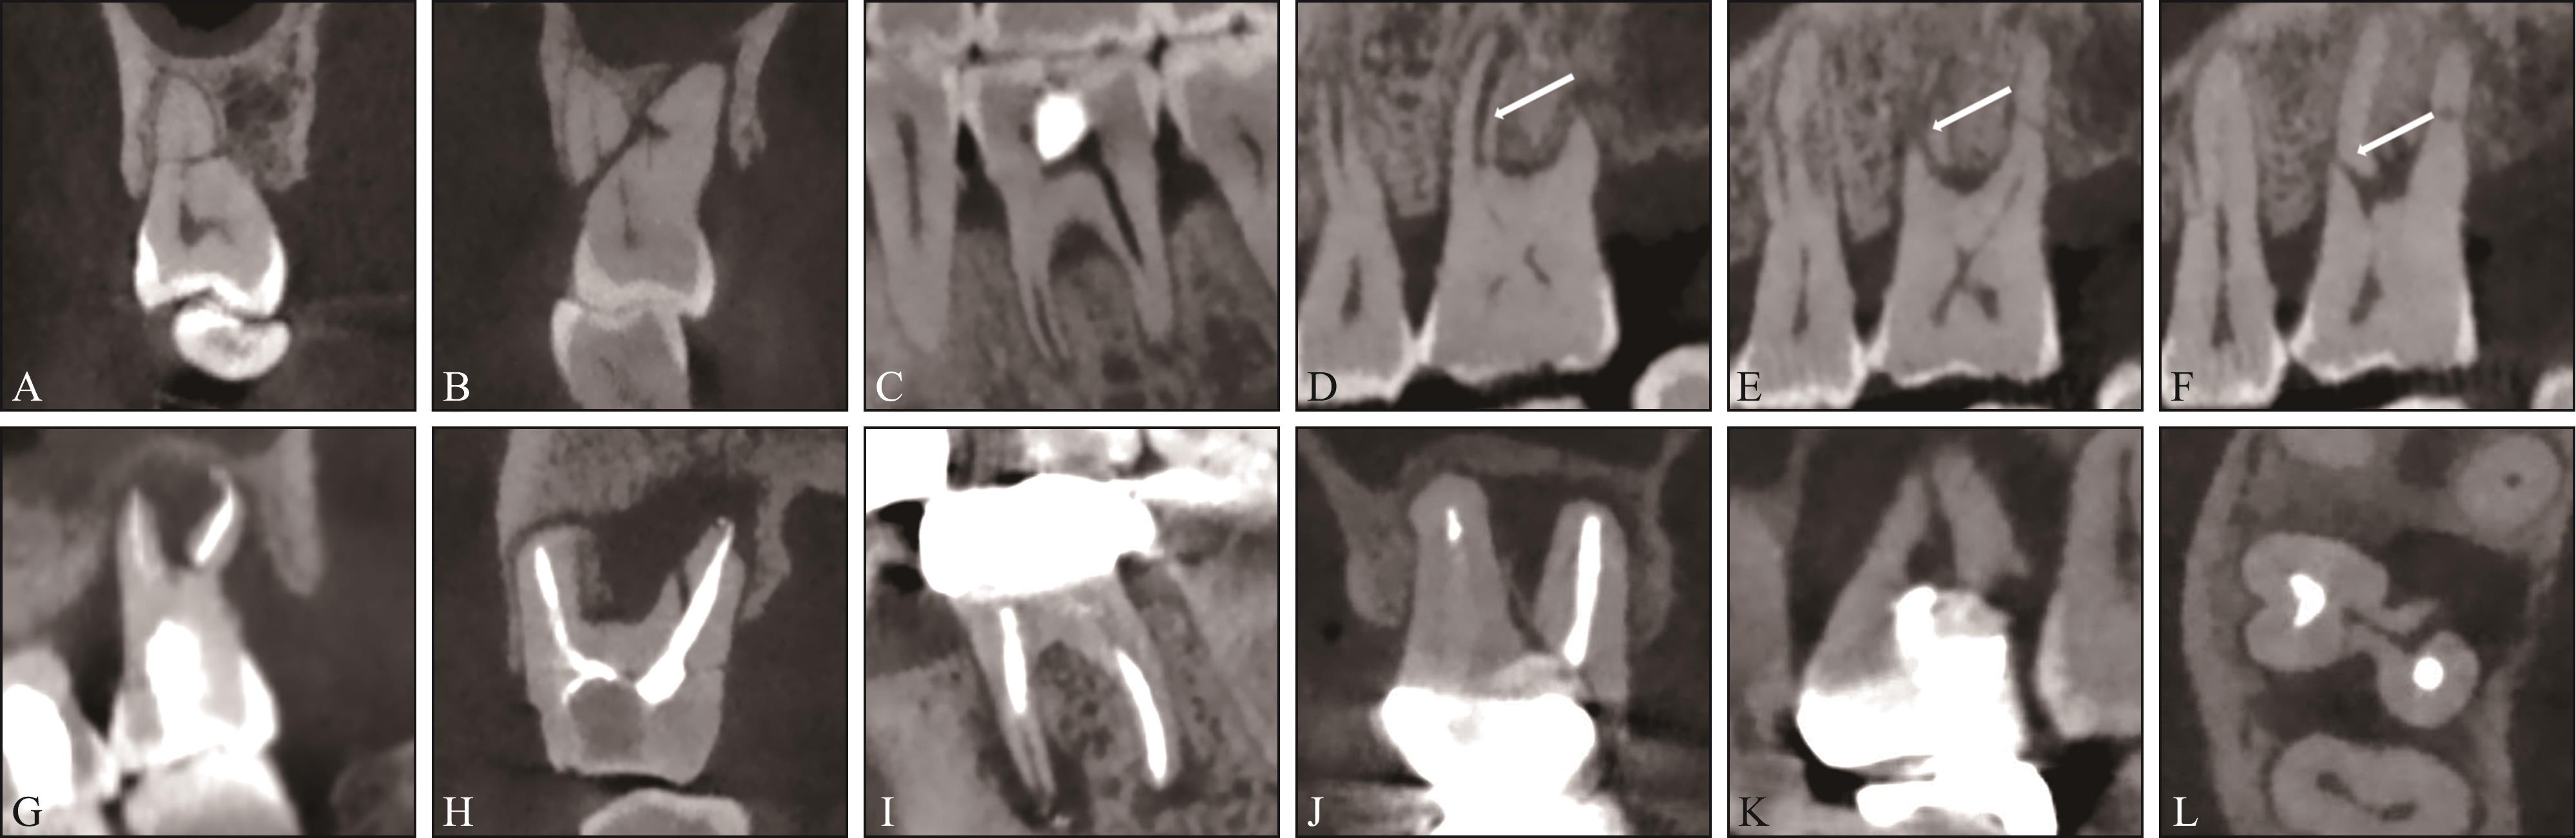

目的 探究根管治疗与非根管治疗根折后牙的临床及锥形束CT(CBCT)特征是否存在差异。 方法 回顾性收集CBCT检查发现的305例患者的340颗根折后牙,根据根折牙是否行根管治疗分为根管治疗牙和非根管治疗牙。记录根折患者的年龄和性别,在CBCT图像上评估根折发生的牙位、牙根位、根折类型(纵折、横折、斜折、不规则折)、牙根纵折方向、横折线位置及根折线周围骨吸收情况。 结果 1)非根管治疗与根管治疗根折的牙位差异有统计学意义(P=0.028)。二者根折的牙位均以上颌磨牙和下颌磨牙为主,但根管治疗牙前磨牙的发生比例(27.2%)高于非根管治疗牙(14.2%)。2)非根管治疗与根管治疗根折的牙根位差异有统计学意义(P=0.037),最常见牙根位均是下颌磨牙近中根(发生率分别为36.4%、32.2%),但排名第二的牙根位分别是上颌磨牙腭根(23.0%)、上颌前磨牙牙根(20.3%)。3)非根管治疗与根管治疗根折牙折裂类型的差异有统计学意义(P<0.001)。非根管治疗牙纵折占比为43.6%,而根管治疗牙纵折占比高达75.6%。4)非根管治疗与根管治疗纵折牙根纵折方向的差异无统计学意义(P=0.58),均以颊舌向为主(86.0%、84.1%)。5)非根管治疗与根管治疗牙横折发生位置的差异无统计学意义(P=0.132),均以根颈1/3区最常见。6)非根管治疗与根管治疗根折折裂线周围骨吸收的差异有统计学意义(P<0.001)。59.0%的非根管治疗根折牙折裂线周围有骨吸收,而根管治疗根折牙中91.8%折裂线周围有骨吸收。 结论 非根管治疗与根管治疗根折牙在临床和CBCT特征上均存在差异,非根管治疗根折牙更加复杂多变的特征表明复杂的咬合因素在根折发生中所起的作用,而根管治疗根折牙更高的一致性表明其根折发生可能与根管治疗对牙齿的结构改变有关。

Objective This study aimed to investigate the clinical and cone beam computed tomography (CBCT) characteristics of root fractures in endodontically versus nonendodontically treated posterior teeth. Methods A total of 340 posterior teeth from 305 patients were retrospectively collected. The fractured teeth were divided into endodontically treated (ET) teeth and nonendodontically treated (NET) teeth. The clinical information (age and gender of patients) was recorded. The type of fractured tooth, fractured root, orientation of fracture lines (vertical, horizontal, oblique, and irregular), direction of vertical fracture lines, location of horizontal root fractures, and bone resorption around fractured roots were evaluated and recorded based on CBCT images. Results 1) The distribution of teeth was significantly different between NET and ET teeth (P=0.028). Root fractures predominantly occurred in mandibular and maxillary molars. However, the proportion of premolars was significantly higher in ET teeth (27.2%) than in NET teeth (14.2%). 2) We observed a significant difference in root distribution between NET roots and ET roots (P=0.037). The mesial roots of mandibular molars were the most common fractured roots in NET and ET roots (36.4% in NET roots and 32.2% in ET roots); however, the second most common roots were the palatal roots of maxillary molars in NET roots (23.0%) and the maxillary premolar roots in ET roots (20.3%). 3) A statistically significant difference in the orientation of root fractures was observed between the two groups (P<0.001). Vertical root fractures accounted for only 43.6% of all root fractures in NET root fractures, whereas they accounted for 75.6% in ET root fractures. 4) For vertical root fractures, the direction of fracture lines between NET and ET root fractures was not significantly different (P=0.58), with both types predominantly presenting as buccal-palatal fractures (86.0% and 84.1%). 5) No significant difference was observed in the location of horizontal fractures between NET and ET root fractures (P=0.132), and the most common site was the cervical third of roots. 6) Bone loss around fractured lines significantly differed between NET and ET root fractures (P<0.001). Around 59% exhibited obvious bone loss around fractured roots in NET root fractures, whereas 91.8% of fractured roots presented bone loss in ET root fractures. Conclusion The NET root fractured teeth and ET root fractured teeth presented quite different clinical and CBCT characteristics. The complex and diverse traits of NET root fractured teeth indicate the influence of multifaceted occlusal factors in their occurrence. By contrast, ET root fractured teeth demonstrate high uniformity, indicating that their occurrence may be related to the structural changes caused by endodontic treatment.